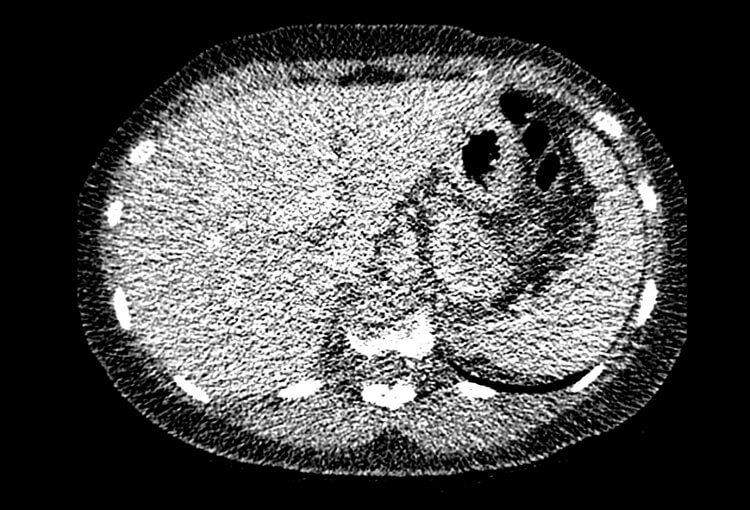

120 kV / 30 mAs / 1mm

Before FBP (Noise 150) VS After ClariCT.AI (Noise 49) 67% Denoising